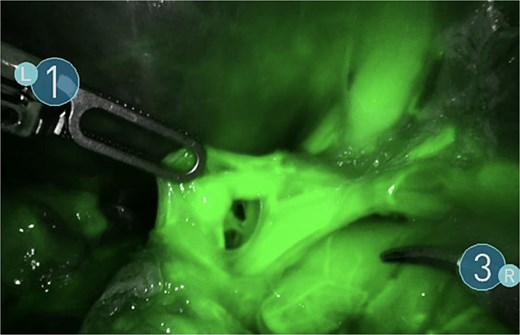

A giant splenic cyst was observed, compressing gastrointestinal organs, with limited mobilization (Fig. 3). Dissection of the splenoepiploic ligaments was performed using a bipolar energy device (Vessel Sealer), followed by dissection of the splenic flexure of the colon. The pre-splenic ligament was divided, and vascular control of the short gastric vessels was achieved. The vascular bed was identified with indocyanine green (ICG)-enhanced fluorescence (Fig. 4), and vascular control of the artery and vein was performed with a 40 mm stapler (Fig. 5). The splenophrenic ligament was divided, and the splenic bed was skeletonized (Fig. 6).

Use of ICG enhanced fluorescence for adequate visualization of splenic hilum.

There are few studies on the use of adjuncts like ICG-enhanced fluorescence for RS, although its benefits have been largely described in other procedures and can be applied for laparoscopic splenectomy [9].

RS is a safe and effective for selected patients, offering enhanced precision, improved visualization, and greater dexterity compared with conventional LS. The use of ICG fluorescence can further aid in accurate vascular identification, contributing to safer dissection in cases with distorted anatomy. In our patient with a giant splenic cyst, robotic assistance allowed for intact specimen retrieval with minimal blood loss and an uncomplicated postoperative course. These advantages support the role of robotic surgery as a valuable option in complex splenic pathology.